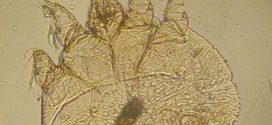

Die Rückkehr der Mini-Monster! Die Milbe, die die Krätze auslöst, ist in Deutschland auf dem Vormarsch – erste Schulen betroffen

BERLIN. Echt eklig, aber nicht gefährlich: In den vergangenen Tagen häufen sich Medienberichte aus ganz Deutschland, wonach die Krätze wieder auf dem Vormarsch ist. Auch die ersten Schulen sind betroffen. „Krätze ist in diesem Jahr in Frankfurt so oft gemeldet worden, wie lange nicht mehr“, so berichtet die Frankfurter Allgemeine Zeitung. „Die Krätze ist zurück“, … Die Rückkehr der Mini-Monster! Die Milbe, die die Krätze auslöst, ist in Deutschland auf dem Vormarsch – erste Schulen betroffen weiterlesen